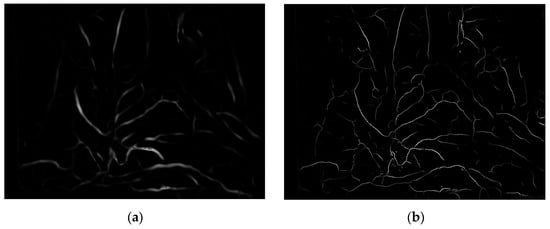

where Iridge represents ridge degree. As shown in Figure 6, (a) is the enhancement result of the Frangi enhancement method, and (b) is enhancement result of this paper method. The blood vessels after single-pixel transformation are thinner and have clearer branches compared to the original method blood vessel images in the human lumen.

Figure 6.

Enhancement results of vascular structure enhancement: (a) the Frangi enhancement method; (b) the method proposed in this paper.